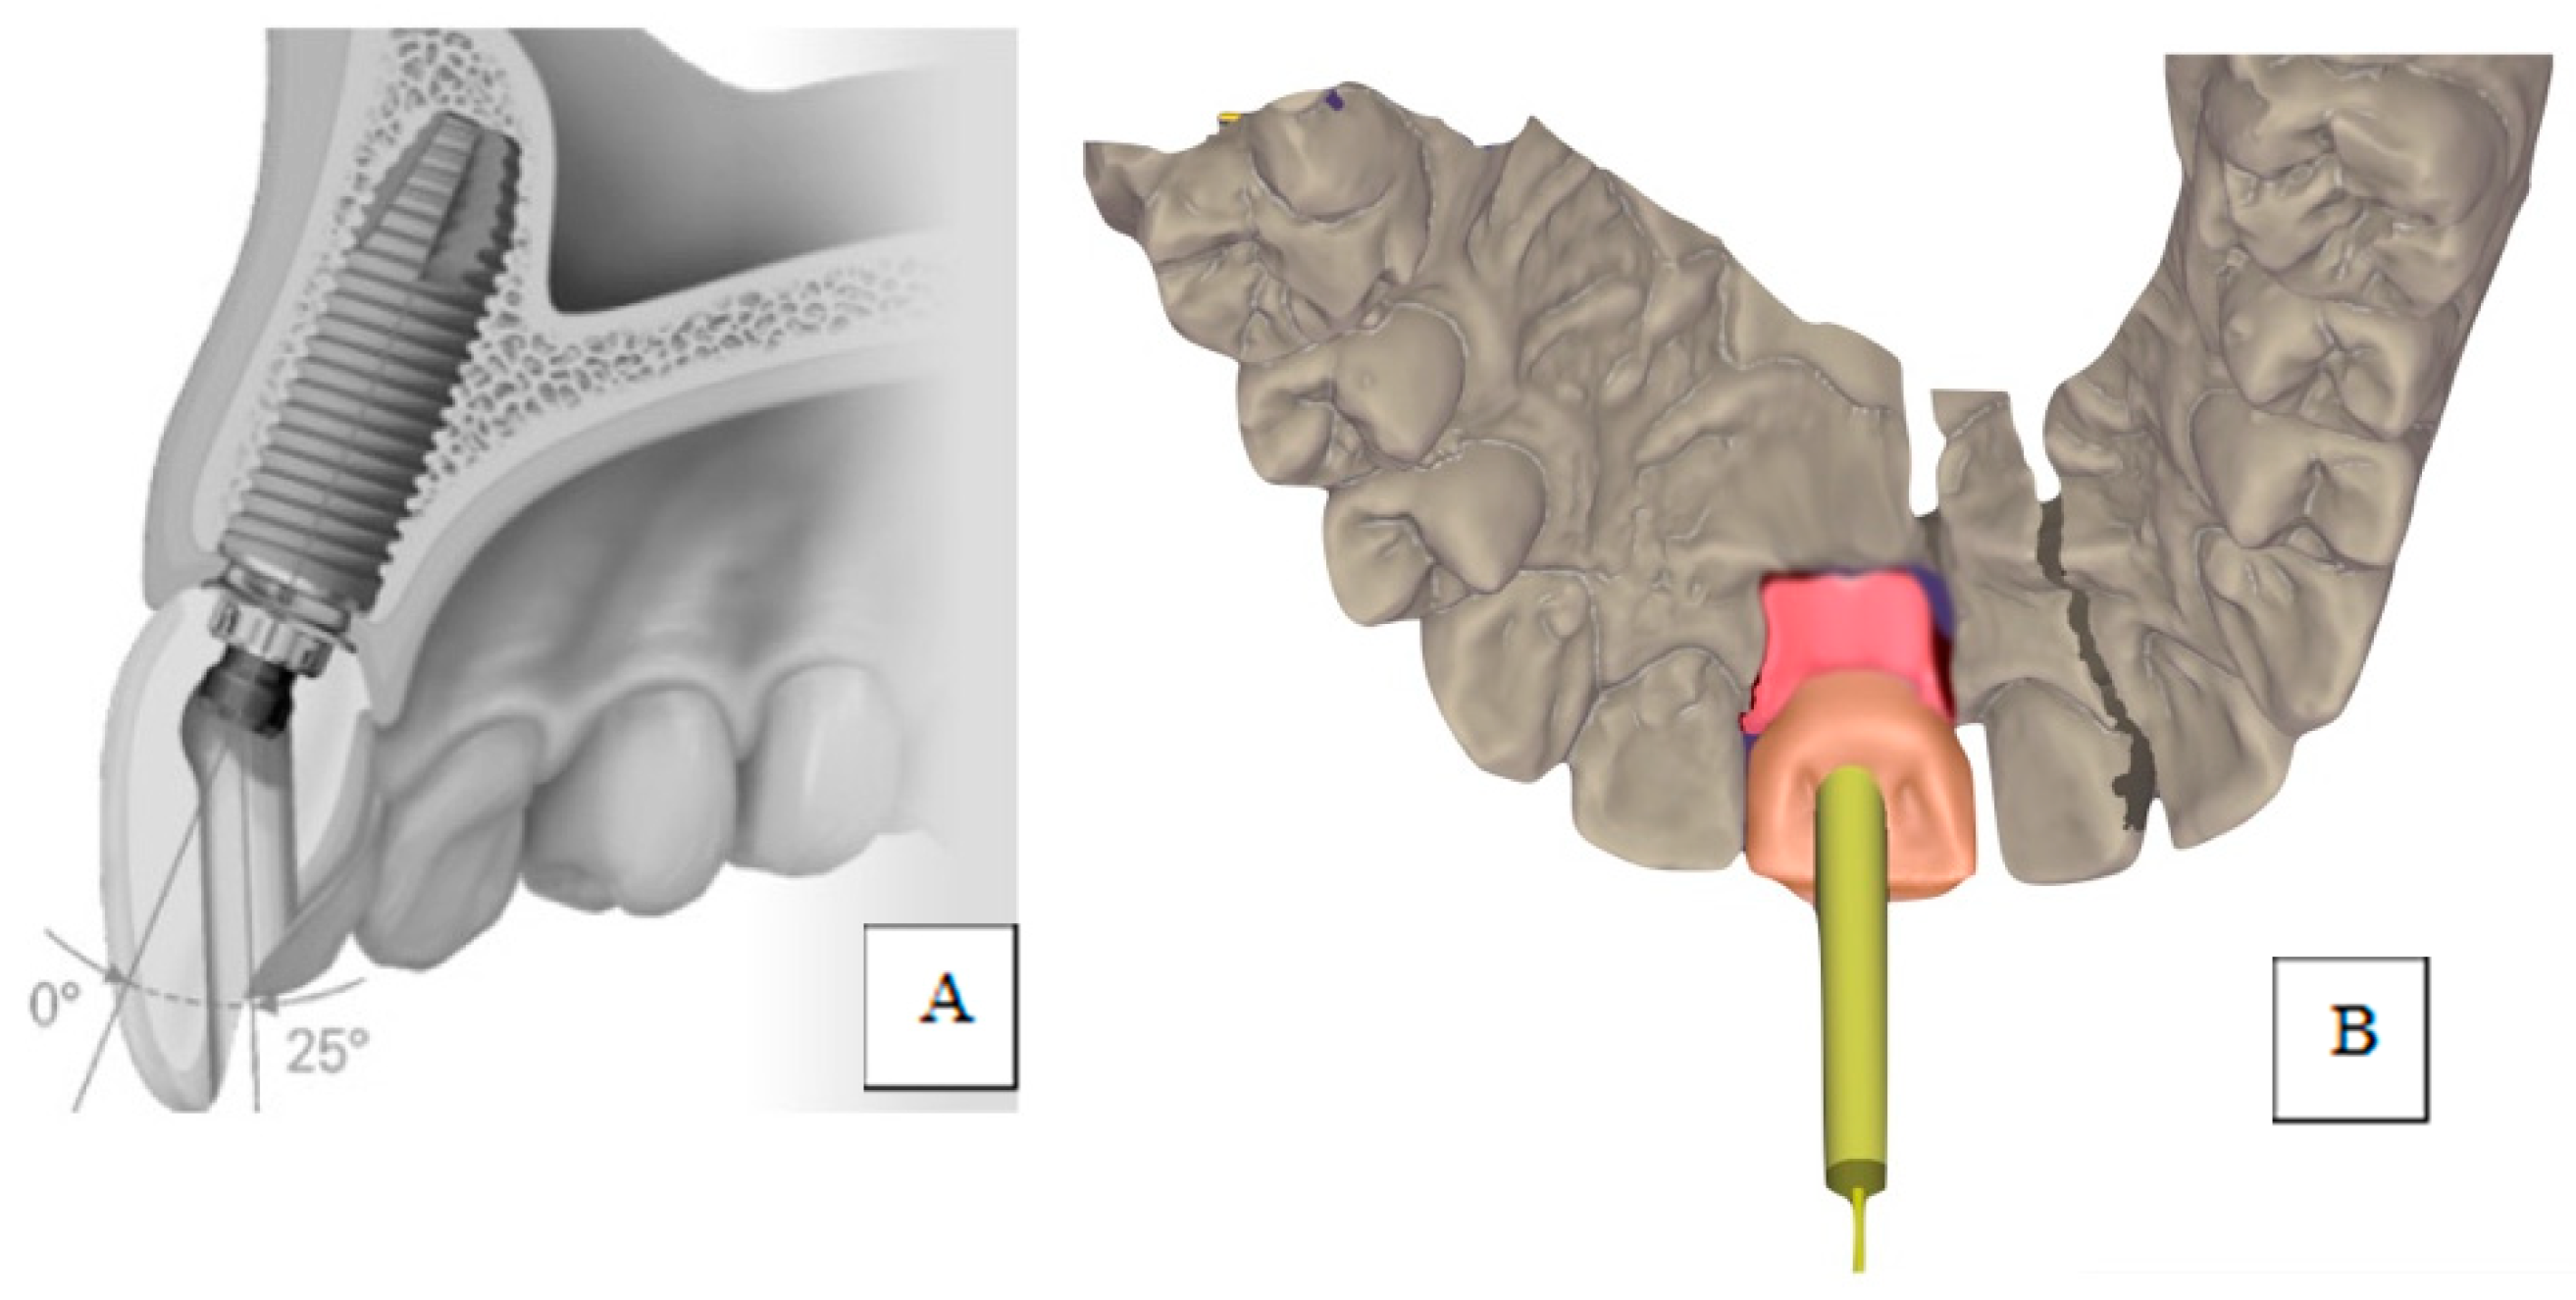

:1. Introduction

2. Materials and Methods